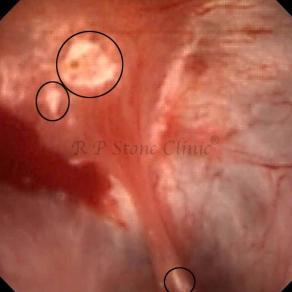

Kidney stone is a solid mass of CRYSTALS. It is the process of crystallization which initiates the formation of kidney stones. This happens in nephrons or units of kidney. Once a small crystal is formed, it can both grow & unite with other crystals leading to the formation of small concretion which eventually forms a stone. Once these large crystals detach from the collecting ducts, the process of stone formation starts in the renal collecting system. A recurrent kidney stone former is advised to know a little bit about something known as Randall’s plaque. Alexander Randall discovered plaques on the renal papillae eight decades back based on examination of 1154 pairs of autopsied Kidneys. He described these renal papillary lesions as cream colored or milk patch areas composed of calcium phosphate & calcium carbonate. These plaques could act as NIDUS for formation of KIDNEY STONE. Calcium Oxalate stone can form on this nidus & then detaches from this plaque to become a free floating stone in the collecting system of kidney

These images are taken as snap shots from the video recording of RIRS Surgery done at our hospital. These are Randall’s Plaques seen with Digital FLEX XC & Digital FLEX XC S. The cream or whitish patches are seen on the tips of RENAL PAPILLAE as seen in images below.

Randall’s Plaques may lead to the formation of Stones.

Those kidney stone patients who have Randall’s Plaques in their kidneys are more likely to form stones again (Recurrent Stones).